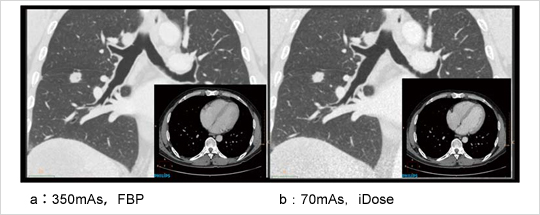

2つの領域でそれぞれ逐次近似再構成(iterative reconstruction:IR)を行うDouble IR法では,Projection Spaceでの逐次近似計算により,低線量での撮影時に目立ちやすいストリークアーチファクトをサイノグラムから除去することも可能である。Image Spaceだけで逐次近似計算を行うSingle IRを採用する場合に懸念される,画質の変化や違和感なども起こさない。これにより,低コントラスト分解能も高コントラスト分解能も犠牲にすることなく,従来の線量に比べ最大80%の被ばく低減を実現している(図4)。

図4 80%被ばく低減画像